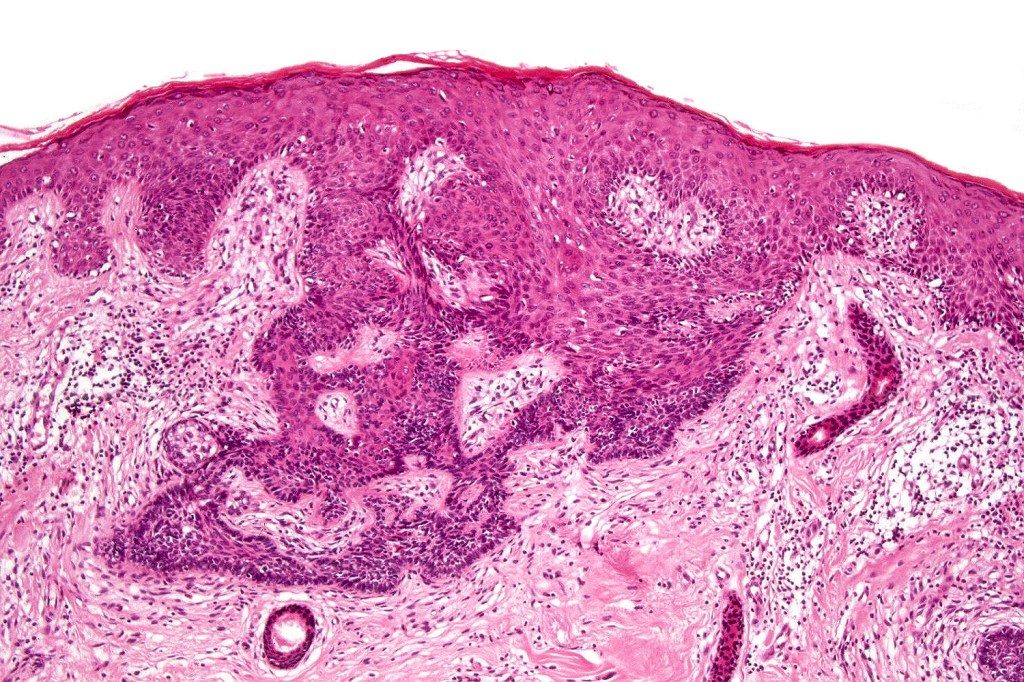

•Sharply circumscribed, unencapsulated nodule in deep dermis +/- subcutaneous fat or deeper (trichoepithelioma is much more superficial)

•Variably sized but generally large, basophilic tumor nodules composed of small uniform basaloid cells with minimal cytoplasm

•Peripheral palisading but no retraction artifact or stromal mucin deposition

•A rich fibromyxoid mesenchymal stroma with variable papillary mesenchymal bodies (sometimes these are absent)